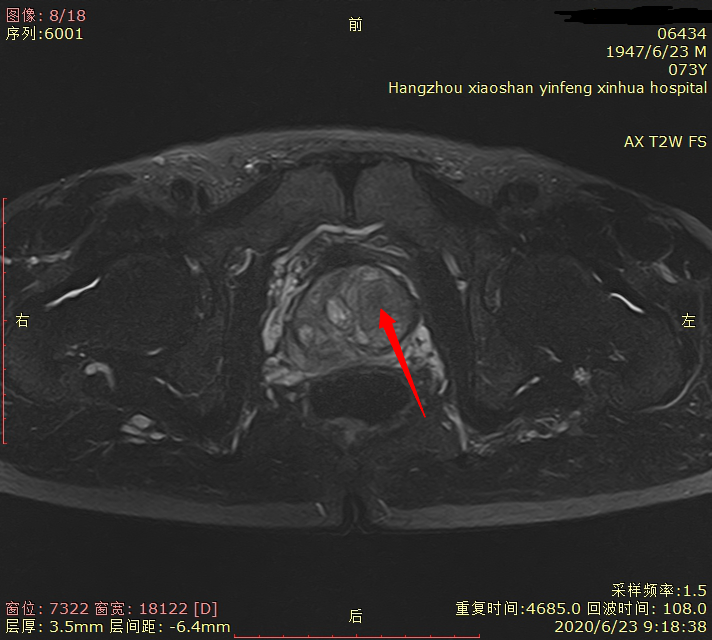

05 磁共振新技术的应用 前列腺弥散加权成像(DWI)对前列腺癌定性诊断有重要意义;可以作为PSA值异常后的常规筛查。